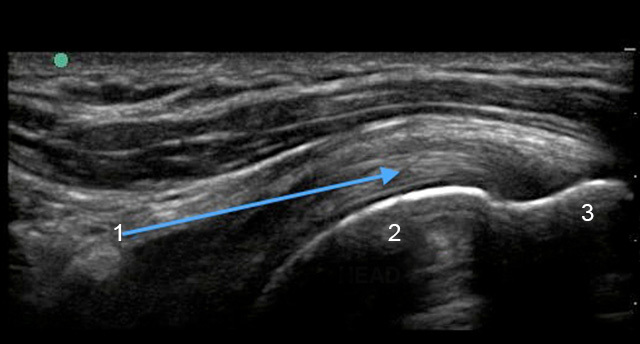

Shoulder Supraspinatus Tendon Longitudinal Image

Supraspinatus

Humeral Head

Greater Tuberosity (GT)